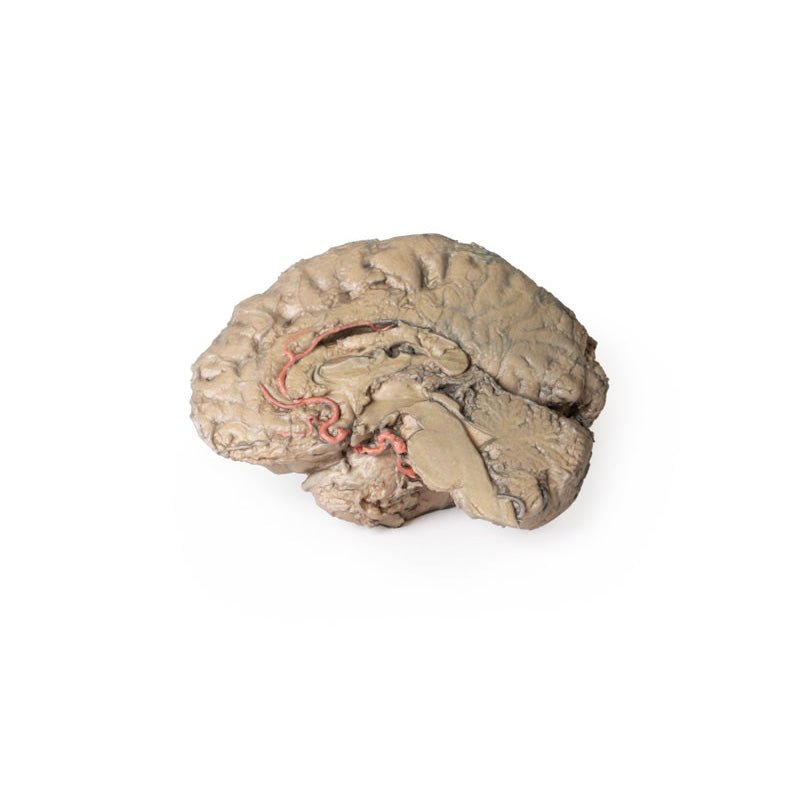

This 3D model is a midsagittal hemisection through a whole brain, preserving the right side anatomy and deep brain

structures and spaces visible in the midline. In lateral view, the right cerebral and cerebellar hemispheres are

covered in the arachnoid mater. In the midline view, the brain regions from the cerebrum to the medulla oblongata

are preserved. Centrally, the third ventricle is opened, with an intact septum pellucidum superiorly positioned and

obscuring the lateral ventricles within the cerebral hemisphere. On the inferior margin of the third ventricle both

the right mamillary body and right optic tract can be observed, whereas posteriorly the cerebral aqueduct can be

observed extending across the midbrain between the tectum and tegmentum towards the fourth ventricle (between the

cerebellum and pons). The cerebellum is separated from the occipital lobe by a preserved portion of the tentorium

cerebelli, and in cross-section the cerebellar cortex helps form the prominent arbor vitae.

A series of arterial

branches have been false coloured to contrast their course across the preserved brain structures. In the midsagittal

view the anterior cerebral artery courses from around the corpus callosum to supply the cingulate gyrus and other

midline cortical regions. The base of the middle cerebral artery can be seen passing deep between the temporal and

frontal lobes, with the posterior communicating artery connecting it to a small remnant of the posterior cerebral

artery. Adjacent to the posterior cerebral is the superior cerebellar artery, extending laterally to pass between

the temporal lobe and the cerebellum before passing deep into the transverse fissure.